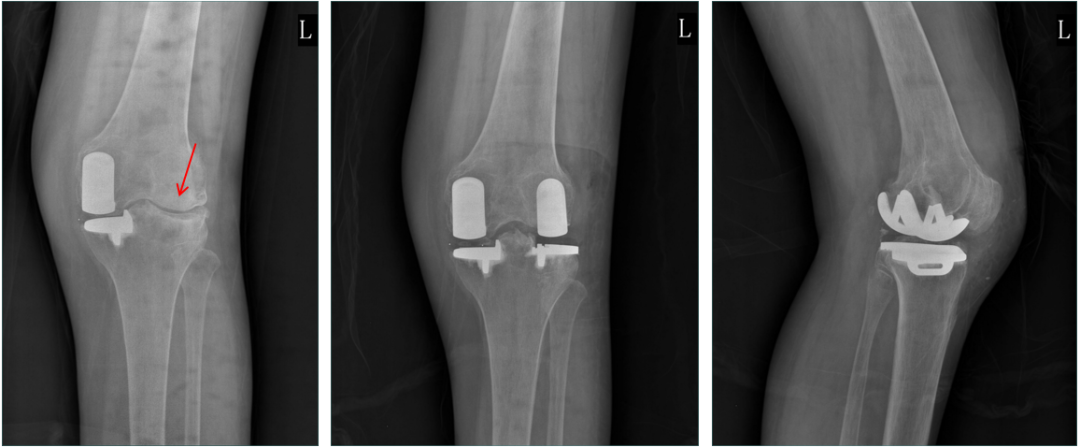

正位片标准胫骨和股骨假体位置

AP位假体位置:胫骨假体无明显内外翻,与胫骨轴线垂直,内侧缘与胫骨平台内侧缘齐平; 股骨假体长轴与胫骨假体垂直,中线一致。

侧位片标准胫骨和股骨假体位置

侧位片假体位置:股骨假体长栓与短栓平行,后倾35°;假体后缘与股骨后髁齐平,胫骨假体后倾7°,与胫骨平台前后缘齐平。

胫骨假体3°内翻

AP位胫骨与股骨假体位置:胫骨假体内翻3°,股骨假体中轴线与胫骨假体垂直。

胫骨假体厚度合适

胫骨垫片厚度合适:术前内翻畸形基本矫正,残留2-3°内翻。

胫骨假体内侧悬挂

AP位胫骨假体位置:胫骨假体内侧悬挂>2mm。

股骨假体偏内放置

AP位胫骨与股骨假体位置:股骨假体轻度内翻,中轴线与胫骨假体中线不一致,偏内侧。

胫骨假体偏大,且后倾不足

侧位胫骨假体位置:胫骨假体后侧悬挂>2mm,后倾2°。

胫骨假体后倾角度大

侧位片胫骨假体位置:胫骨假体后倾12°,前后缘齐平 。

股骨假体偏小

侧位片股骨假体位置:股骨假体偏小,与胫骨假体后缘不齐平;屈曲15°,未包容股骨后髁。

股骨假体偏大

侧位片股骨假体位置:股骨假体与胫骨假体不匹配,股骨假体大一个型号,屈曲45°,后缘空虚。

股骨假体屈曲角度大

侧位片股骨假体位置:股骨假体与胫骨假体匹配,股骨假体屈曲62°,前缘翘起。